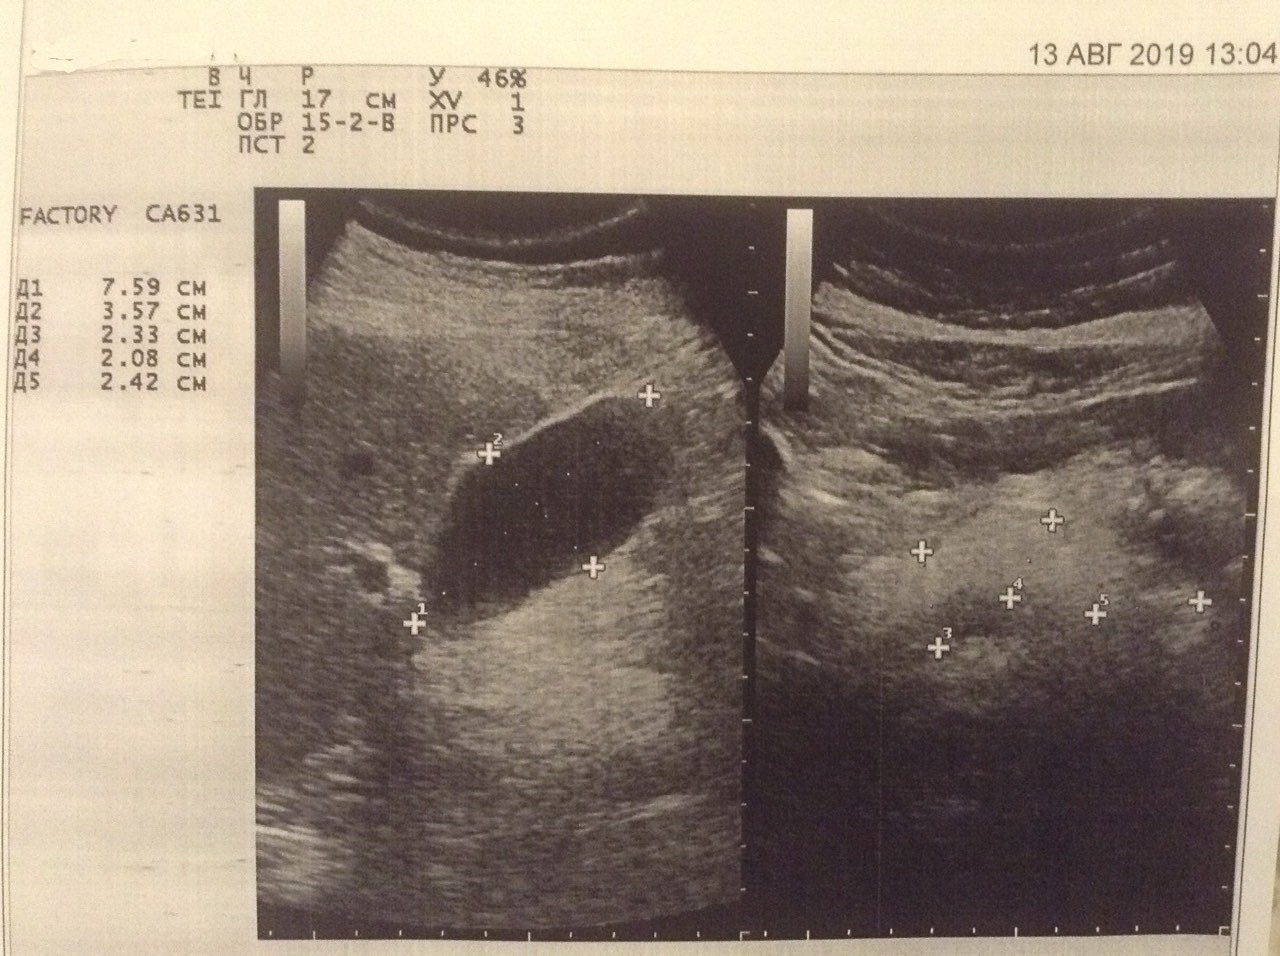

Здравствуйте, все. Закончила лечение в декабре 2018 года. В марте и июле вирус не выявлен. Билирубин, АЛТ и АСТ снизились до нормы. АСТ чуть больше 30, но врач сказал, что это терапевтический показатель. Сделала узи. Доктор, который делала обследования, без комментов отдала результат. По сравнению с прошлым годом : толщина левой доли была 67, сейчас 73, правая была 133 сейчас 142. ((( воротная Вена без изменений - 140. Селезеночная была 8 сейчас 6. Прошлый раз был в области ворот печени лимфоузел сейчас нет. На фото, прикрепленное к описанию, темное пятно выделено. Пожалуйста, расшифруйте,что за фото и что за пятно. И что значит дополнительная долька на селезенке. Буду очень благодарна за ответ.